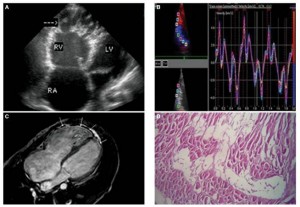

致心律失常型右室心肌病 (A) 经胸壁超声心动图示四腔心,可见右心室扩张及右室心尖部膨出的室壁瘤,伴多发间隔(箭头所示)(B) 组织多普勒速度曲线示收缩期及舒张早期速度减慢,底-中-尖梯度消失(base-mid-apex gradient) (C)MRI心脏长轴图像示右室壁和左室心尖部广泛增强的脂肪信号(箭头所示)(D) 右室壁组织切片染色示心肌细胞被纤维脂肪组织替代(H-E, x100)。(图)